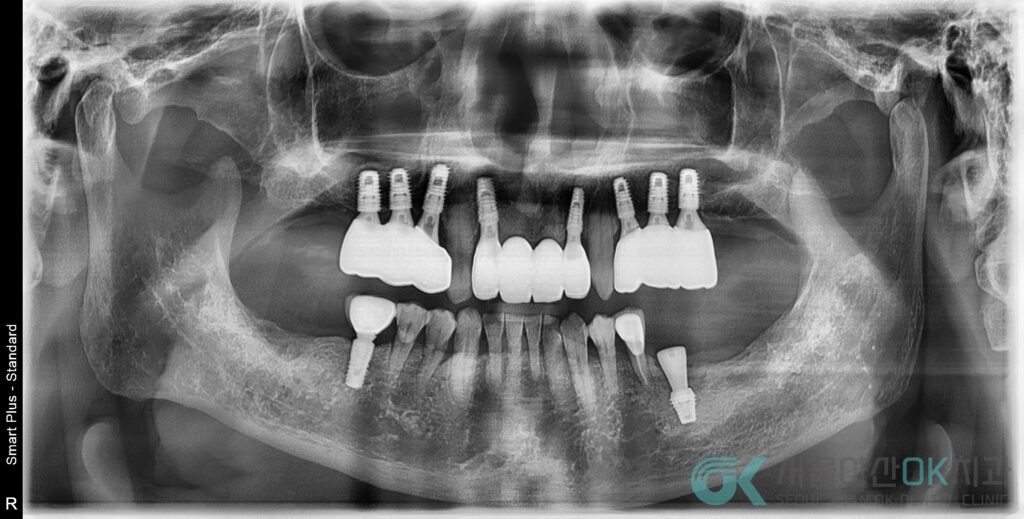

① 시술 1개월 후

임플란트 시술 1개월 후 임플란트 주변 X-ray 촬영을 통해 시술 부위에 이상이 없음을 확인했는데요.

다만 잇몸이 아물면서 임시치아 밑으로 약간 틈이 생겨 이부분은 잇몸이 보다 더 진정이 되면 메우기로 했습니다.

② ISQ 측정 및 프렙

또한 앞서 치료를 진행한 #12 #22도 골유착 상태가 매우 양호한 것으로 확인되었는데요.

그래서 전치부 지르코니아 보철을 위한 프렙 & 인상채득을 진행하였습니다.